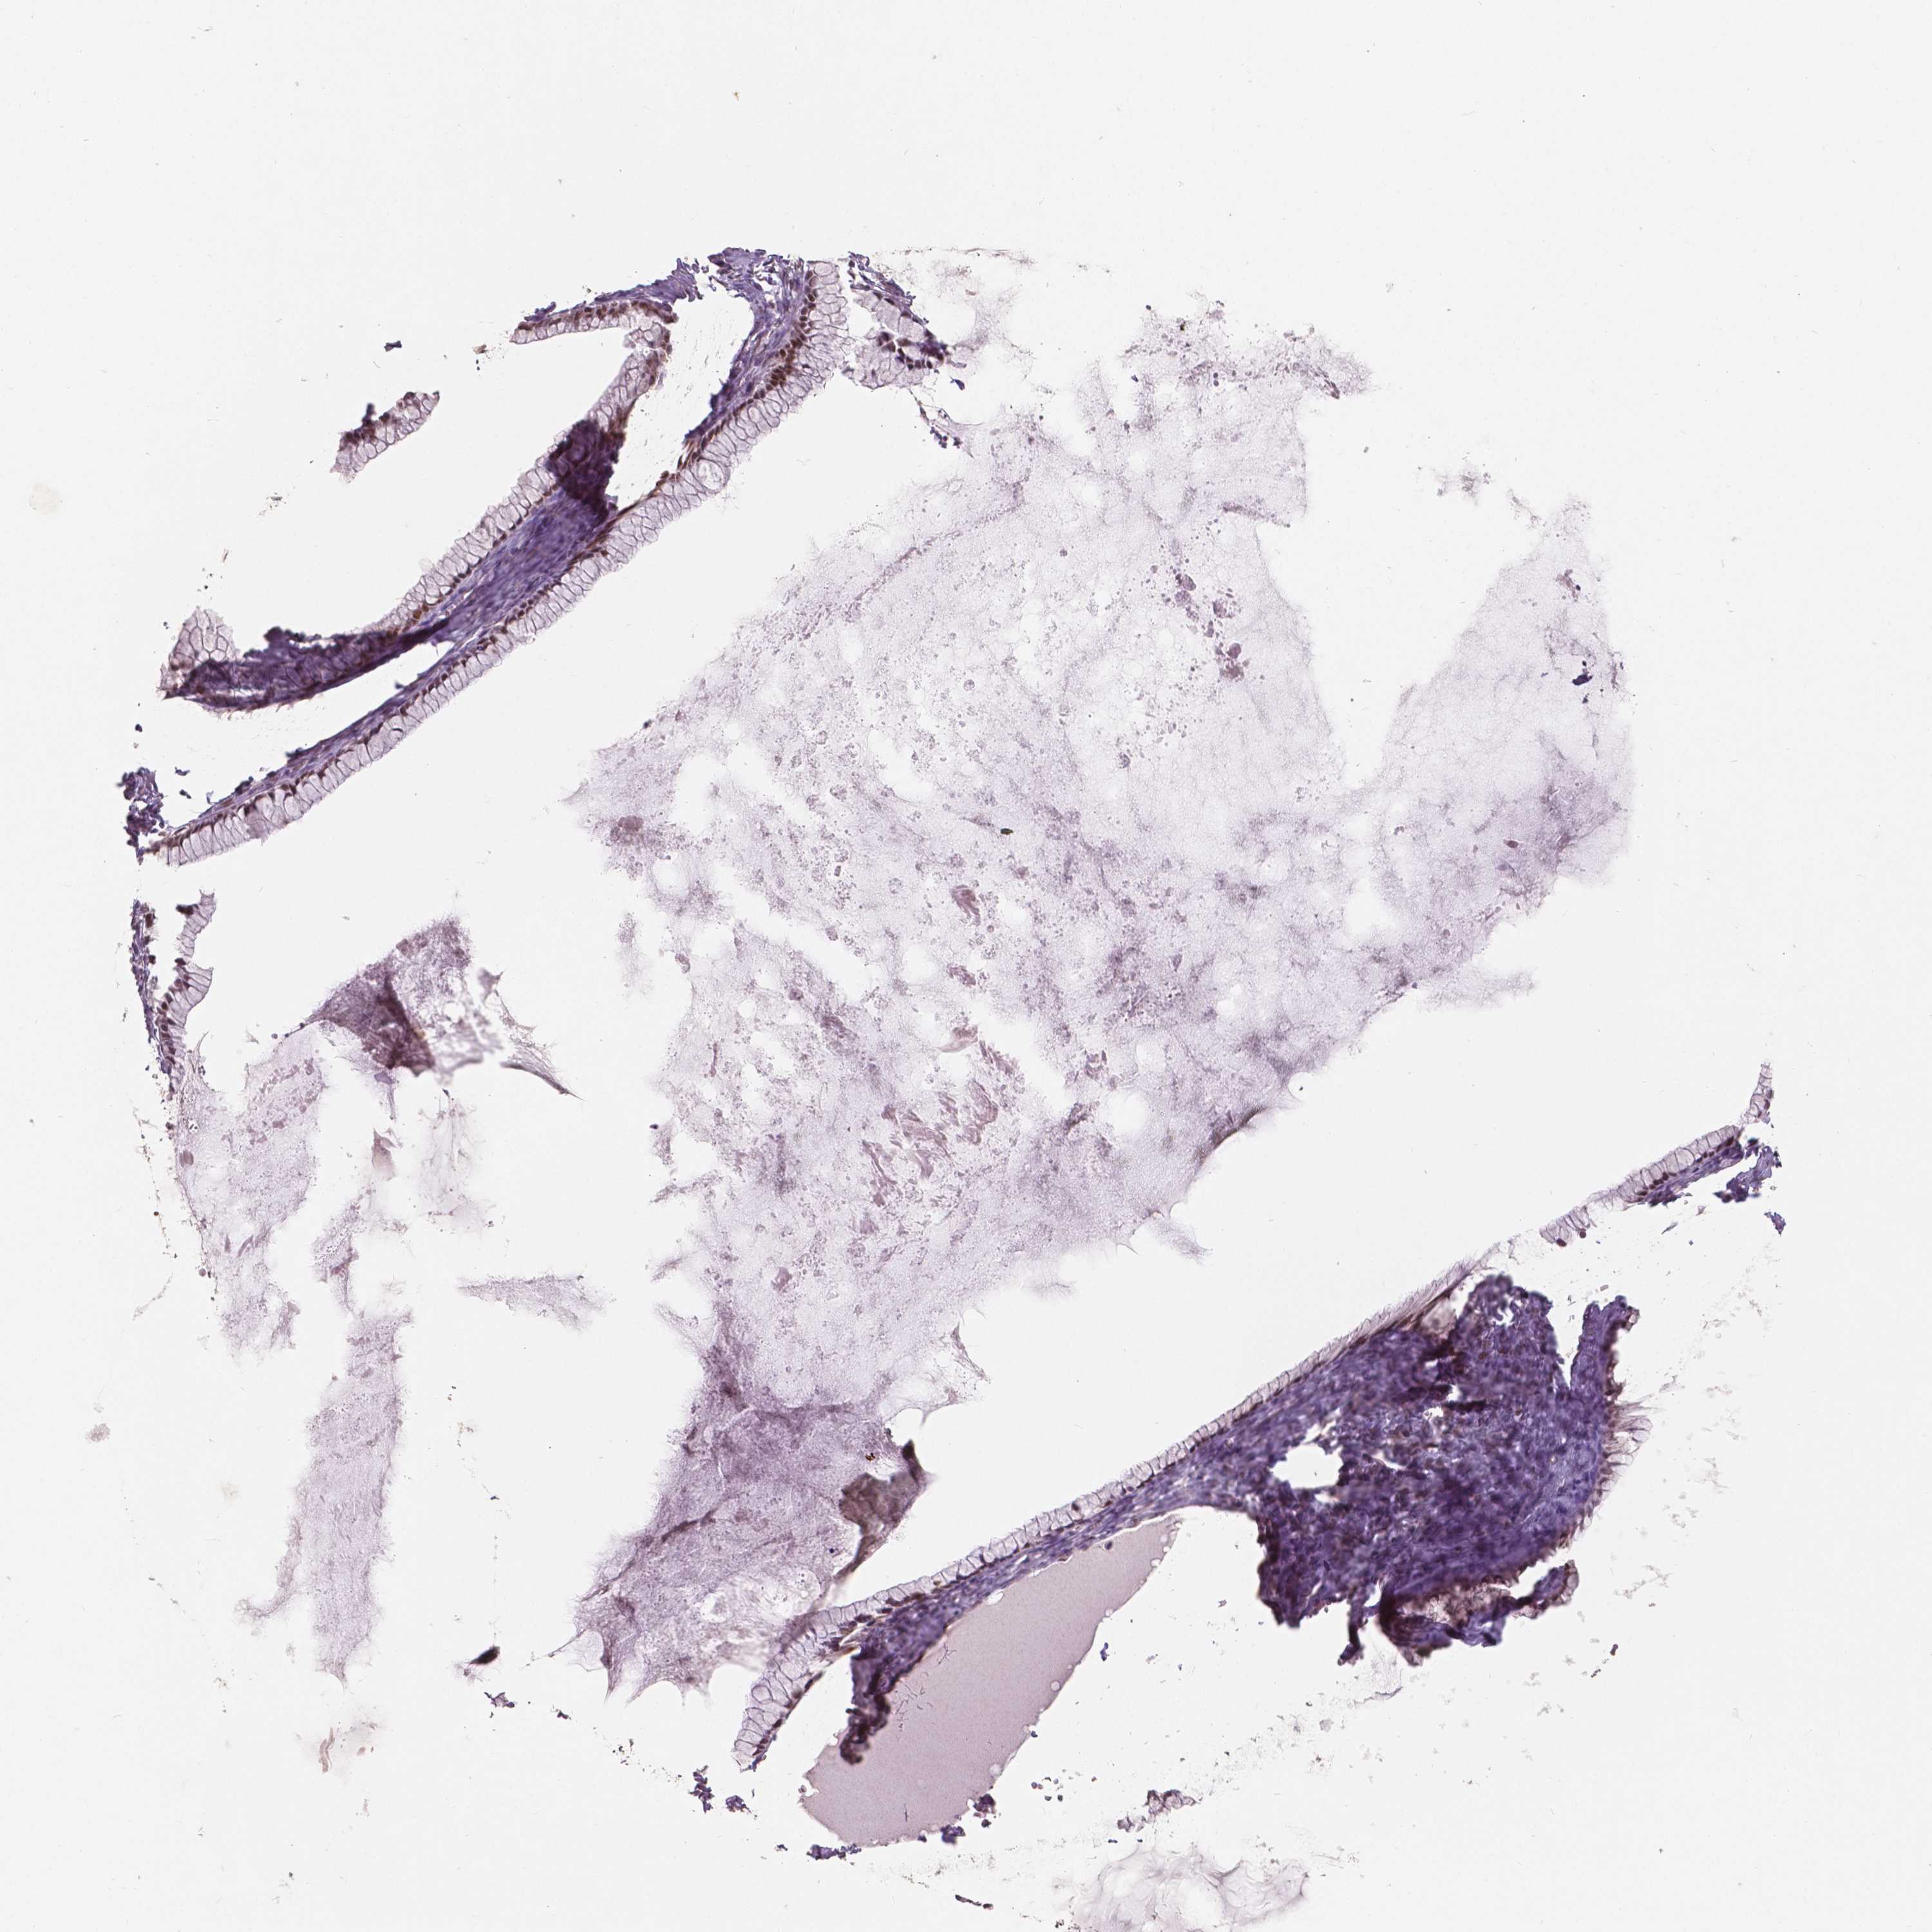

OVARIAN CANCER - Protein expressioni

A mouse-over function shows sample information and annotation data. Click on an image to view it in a full screen mode. Samples can be filtered based on level of antibody staining by selecting one or several of the following categories: high, medium, low and not detected. The assay and annotation is described here.

Note that samples used for immunohistochemistry by the Human Protein Atlas do not correspond to samples in the TCGA dataset.

Antibody stainingi

Antibody staining in the annotated cell types in the current human tissue is reported as not detected, low, medium, or high, based on conventional immunohistochemistry profiling in selected tissues. This score is based on the combination of the staining intensity and fraction of stained cells.

Each image is clickable and will lead to virtual microscopy that enables deeper exploration of all samples and also displays staining intensity scores, fraction scores and subcellular localization as well as patient and tissue information for each sample.

Antibody HPA015801

Antibody CAB068246

Antibody CAB068247

Staining

High

Medium

Low

Not detected

Cystadenocarcinoma, serous, NOS

Cystadenocarcinoma, mucinous, NOS

Carcinoma, endometroid